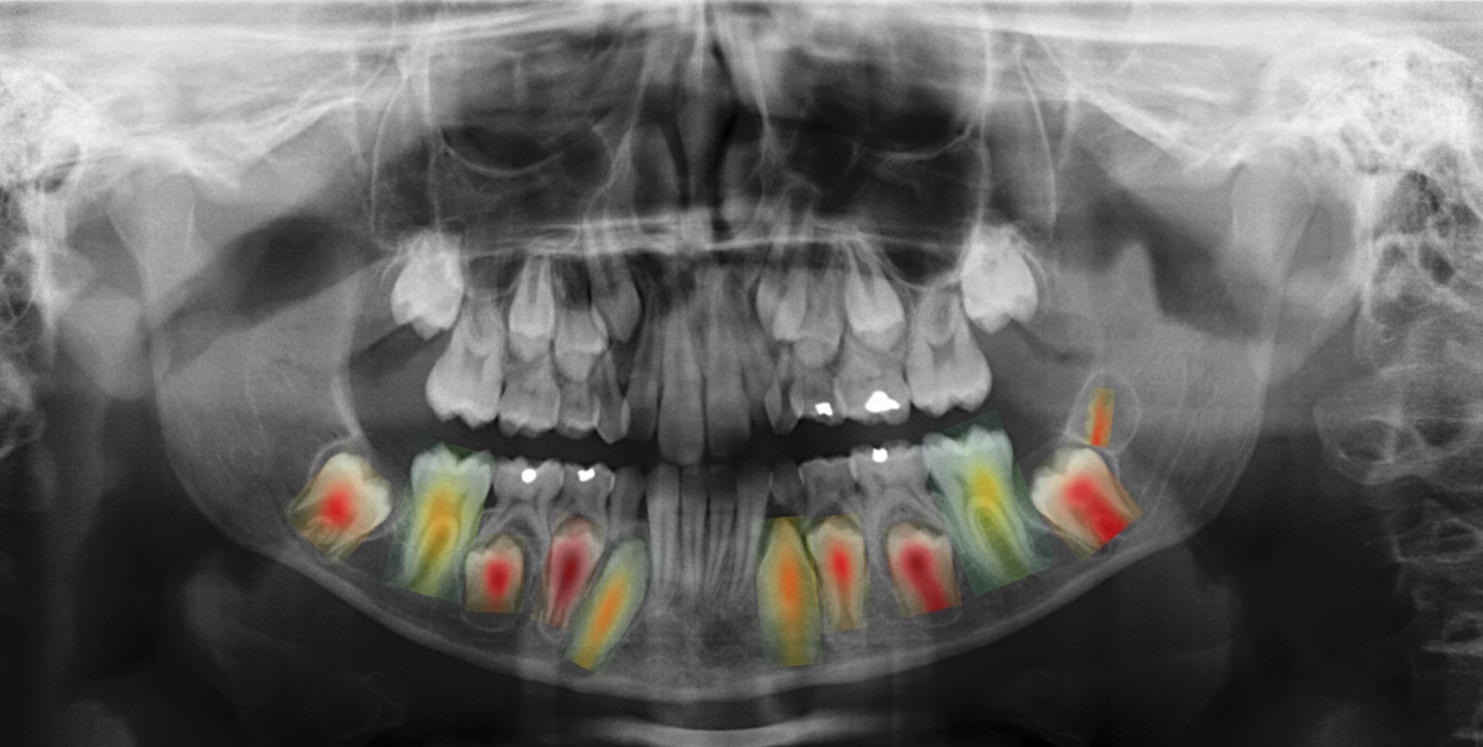

“O primeiro foi desenvolver unha metodoloxía para estimar a idade e o sexo a partir da radiografía completa, un paso preliminar que nos permitiu acadar unha precisión superior á dos métodos existentes”, explica Nicolás Vila. “Empregamos métodos baseados en mapas de calor para determinar as rexións da radiografía máis relevantes cando tratamos de estimar a idade”, prosigue o autor da tese. “Deste xeito, confirmamos o coñecemento adquirido nos estudos clínicos previos, que afirmaban que a rexión dental é a que máis inflúe na predición final”, afirma o investigador posdoutoral. O traballo, dirixido polas científicas María José Carreira e Inmaculada Tomás, contou tamén coa colaboración das odontólogas Paulina Varas e Ángela Aneiros.

Por último, o equipo de traballo desenvolveu unha nova metodoloxía para detectar as pezas dentais presentes na radiografía, co obxectivo de usalas no proceso de estimación. A investigadora María José Carreira explica como “tras estimar a idade e o sexo de cada dente por separado, as predicións individuais resultantes combínanse, para obter unha única estimación global”. “Grazas a esta integración temos un sistema altamente explicable, xa que en todo momento é posible saber en que dente confiar máis, e en cal menos”, destaca a investigadora do CiTIUS. Ademais, e para reforzar esta capacidade de interpretación, o sistema proporciona mapas de calor adicionais, destinados a avaliar as zonas de cada dente que máis inflúen na predición final.